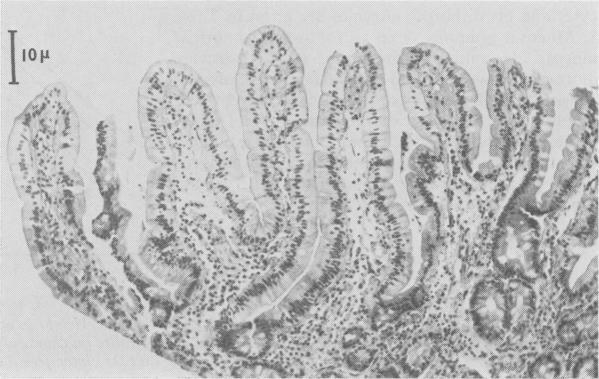

Duodenal mucosa showed normal morphology, interepithelial lymphocytes, alkaline phosphatase, and sucrase in a girl with growth retardation and iron deficiency, but normal absorption of lactose and xylose after two years of abnormal stools. Mucosal lactase was low. Fourteen months later mucosal damage consistent with coeliac disease was evident, and gluten intolerance was subsequently confirmed by gluten challenge. It is probable that, in some children, the mucosal lesion occurs very gradually, so that at an early stage with normal morphology, suppression of lactase activity and possibly interference with iron absorption may be the only abnormalities.

一名生长发育迟缓且缺铁的女孩,十二指肠黏膜形态正常,存在上皮间淋巴细胞、碱性磷酸酶和蔗糖酶,但在两年大便异常后乳糖和木糖吸收正常。黏膜乳糖酶水平较低。14个月后,出现了与乳糜泻相符的黏膜损伤,随后通过麸质激发试验证实了麸质不耐受。在一些儿童中,黏膜病变可能进展非常缓慢,以至于在早期形态正常时,乳糖酶活性受抑制以及可能对铁吸收的干扰可能是仅有的异常表现。